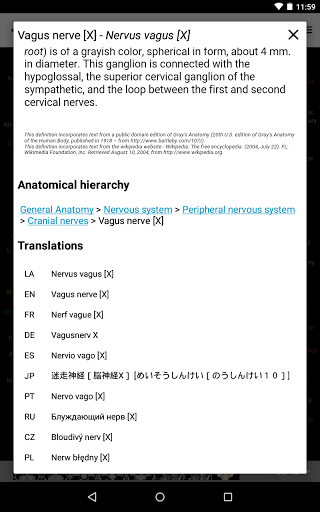

e-Anatomy tiene más de 26 000 imágenes que contienen series de imágenes en vistas axiales, coronales y sagitales, así como radiografías, angiografías, imágenes de disección, gráficos anatómicos e ilustraciones. Todas las imágenes médicas fueron etiquetadas cuidadosamente, más de 967 000 etiquetas disponibles en 12 idiomas, incluida la Terminologia Anatomica latina.

- Cambie de idioma con solo tocar un botón